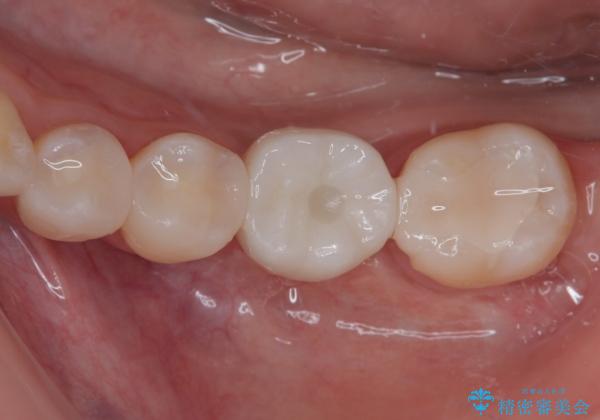

- ブリッジの歯のないところにインプラントを入れて、銀歯を白くやり替えたいと来院された患者様です。

歯の欠損している箇所にはインプラント治療をし、銀歯と仮詰めの部分はセラミックインレーにて補綴することとしました。

すべての治療の前に親知らずの抜歯も行っています。